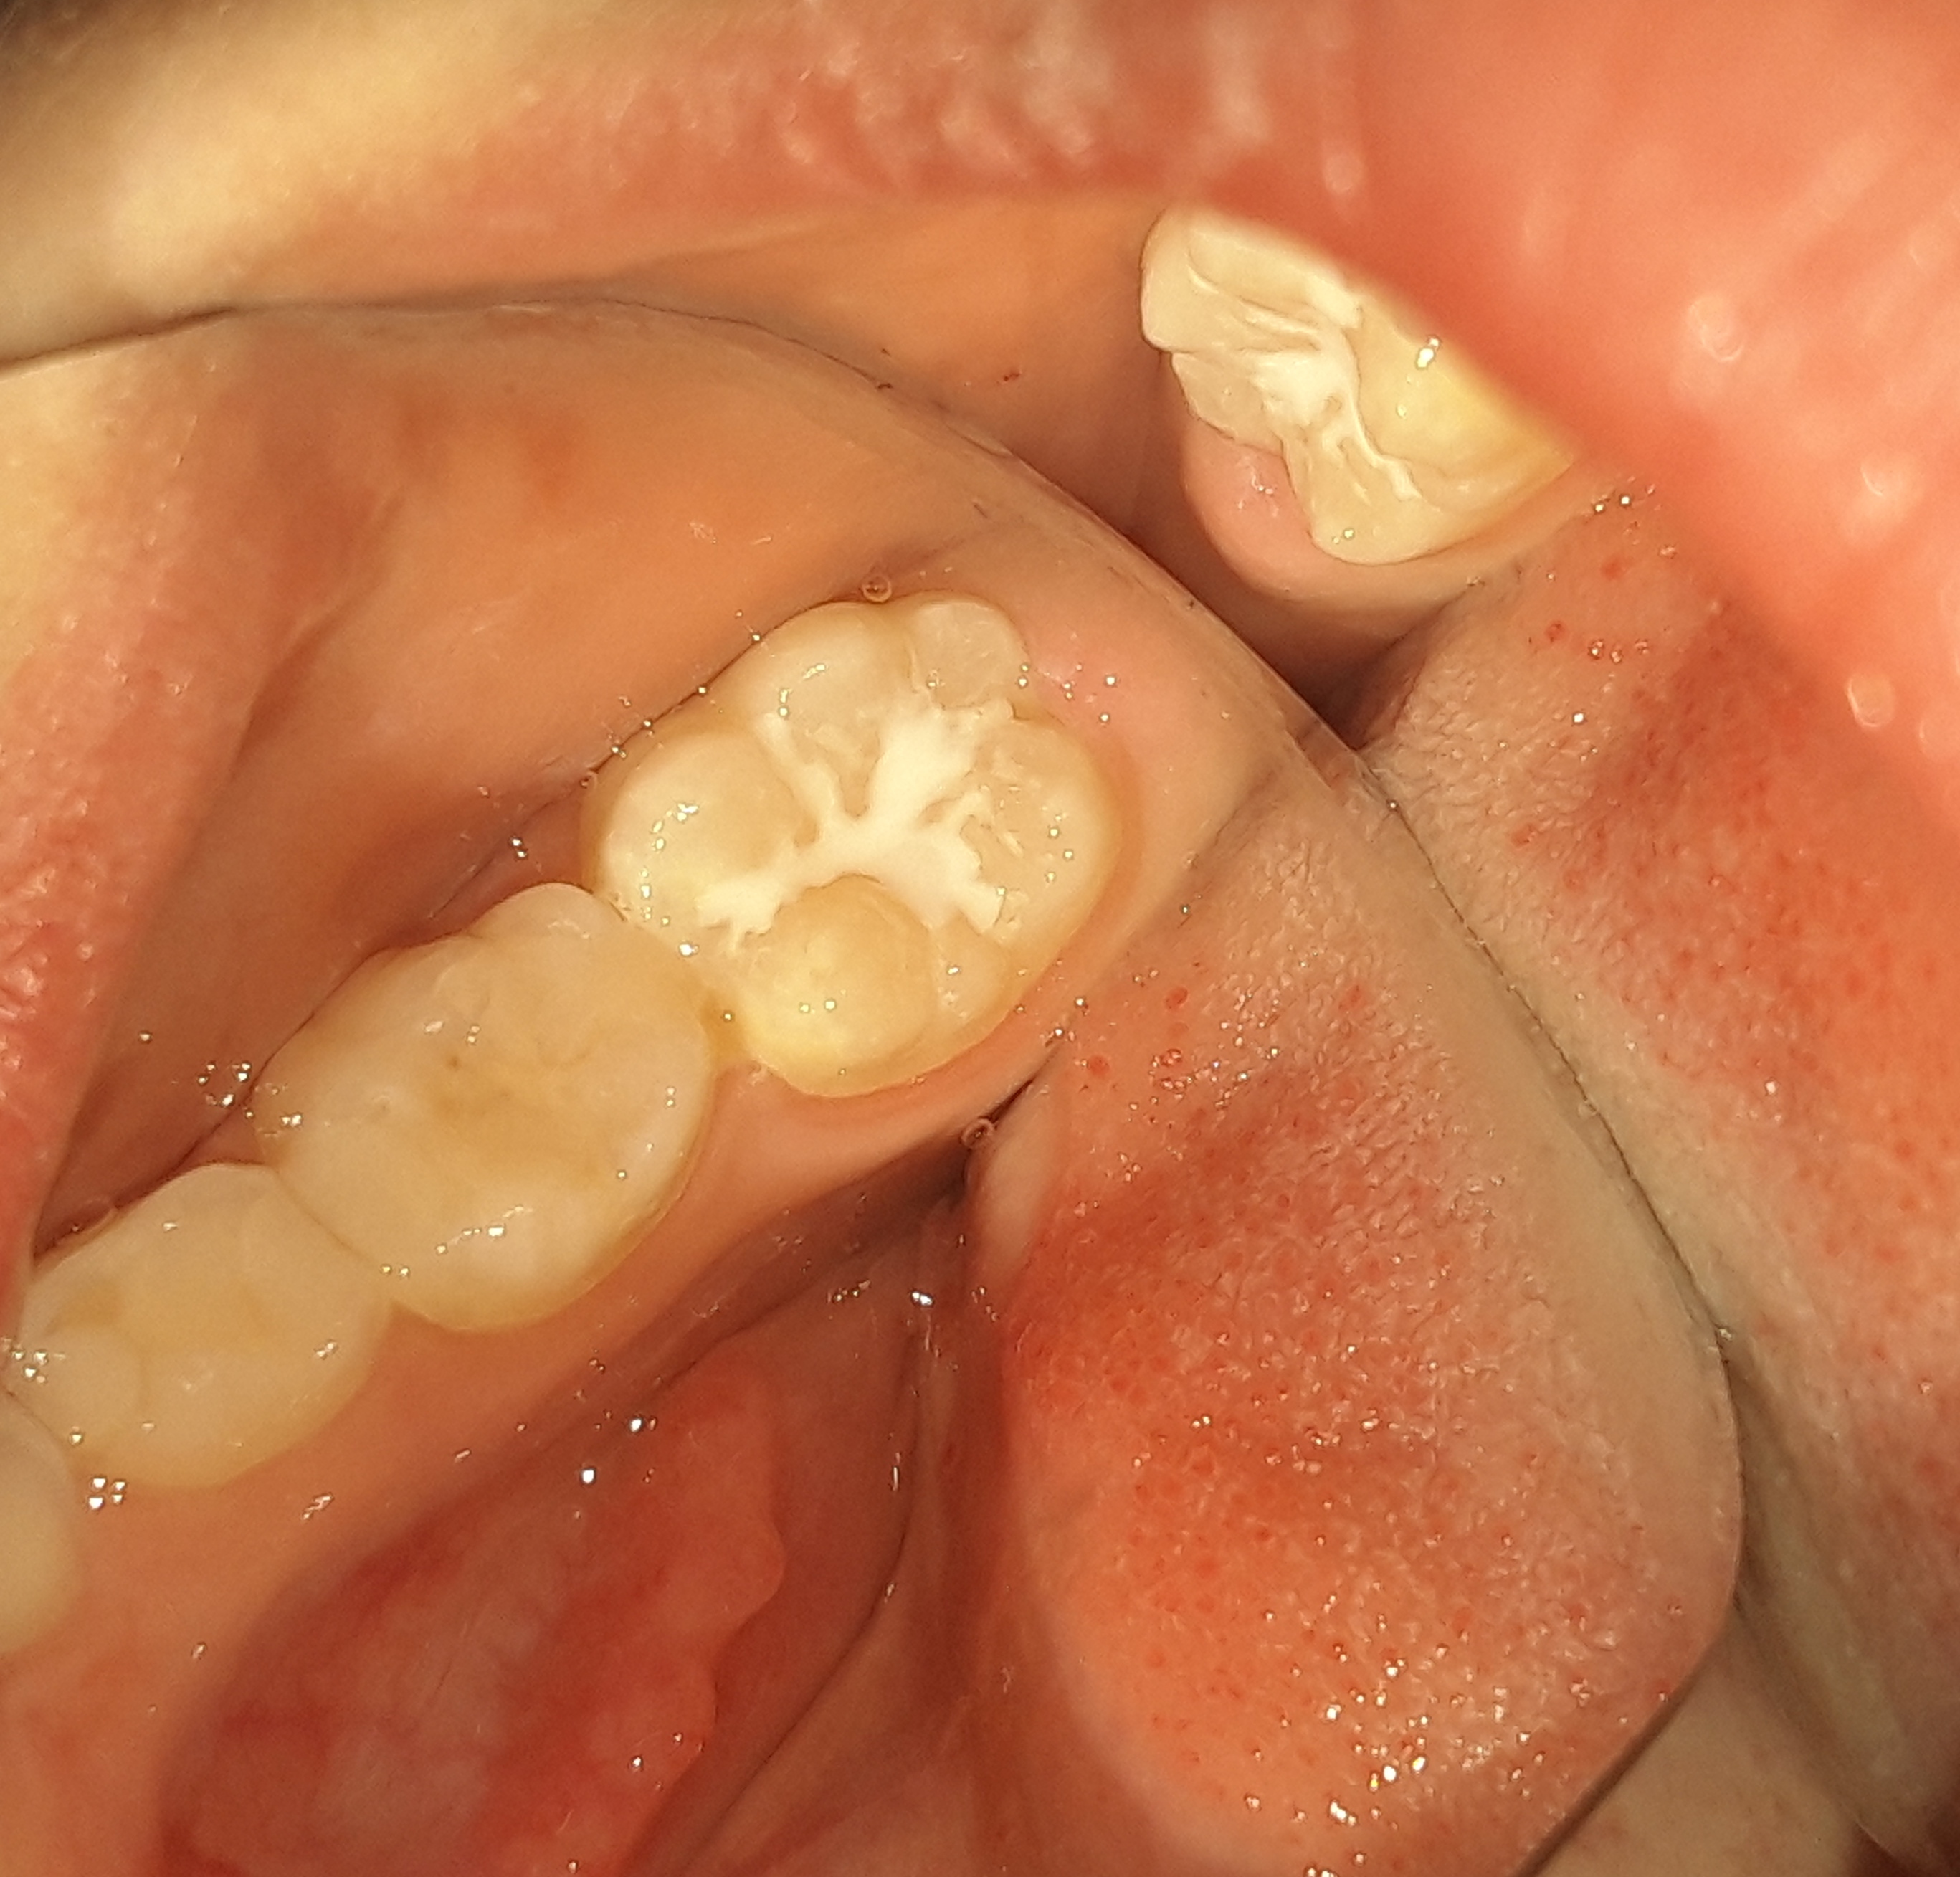

ΠΡΙΝ

ΜΕΤΑ

Η μικρή ασθενής προσήλθε για τον τυπικό ετήσιο έλεγχο. Συστήθηκε η προληπτική κάλυψη των δεύτερων μόνιμων γομφίων (sealant), δεδομένου οτι το κορίτσι είχε ήδη 4 σφραγισμένα δόντια και επομένως υπάρχει τερηδονική δραστηριότητα στο στόμα της. Με την προληπτική κάλυψη των δοντιών προστατεύονται οι μασητικές επιφάνειες αυτών από πιθανό τερηδονισμό τους.Τα sealants είναι καλό να γίνονται σε όλους τους μόνιμους γομφίους των δοντιών. Η πρόληψη είναι η καλύτερη θεραπεία.